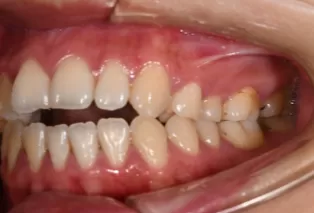

Photos intra-orales